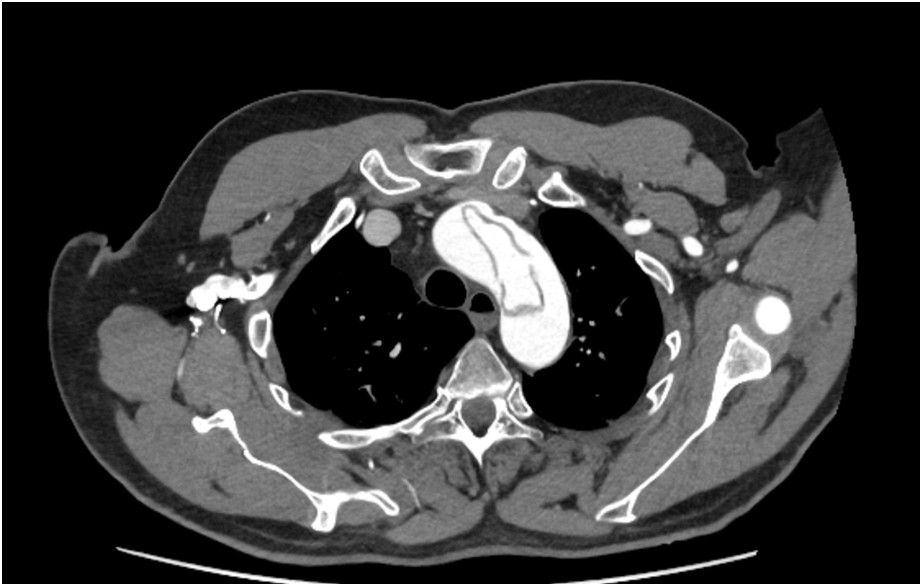

Na podstawie załączonej zdjęcia z badania tomografii komputerowej pacjenta rozpoznasz: